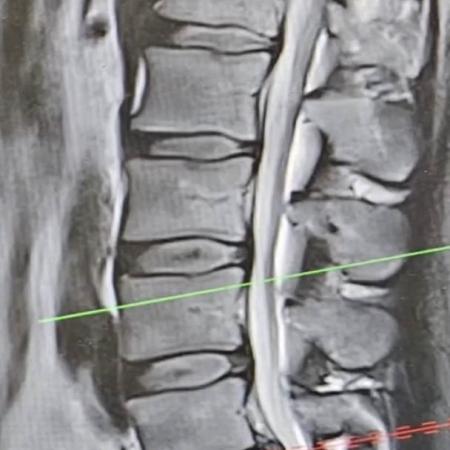

Turek se vyjádřil i ke svému zdravotnímu stavu. Upřesnil, že má „poměrně drsně“ vyhřezlou ploténku. V neděli byl podle svých slov na magnetické rezonanci. Vysvětlil, že před několika dny prakticky přestal chodit. Dostával infuze a silné léky na bolest. S ploténkou měl potíže už v minulosti.